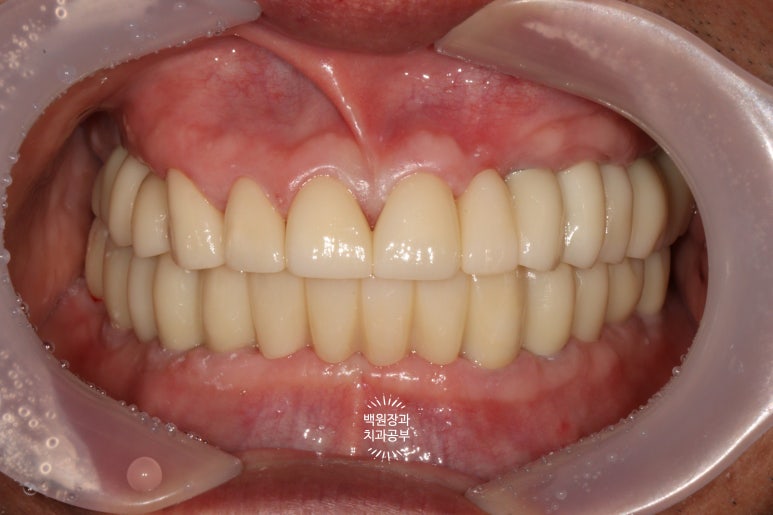

대망의 최종 보철물 완성 후!!!

최종 보철물로 완전히 교체 후 구강내 사진입니다.

순차적으로 포스팅을 읽으신 분들은... 첫 모습을 이미 까먹으셨을텐데요...

처음 내원시 구강내 사진을 생각하신다면!!! 정말 놀라운 변화가 아닐 수 없죠...

제자리를 잃어버렸던 치아들이 모두 가지런하게 되었고,

치아 사이의 벌어진 틈은 지르코니아 보철물을 이용해서 모두 깔끔하게 채워드렸으며,

치아의 색상 또한 60대 남자 환자분의 피부색에 맞추어 어울리게 그리고 화사하게 바꿔드린 상태입니다.

금속색 하나 비춰보이는 것 없이 완벽하네요....

역시 저희 치과의 보철과 전문의 원장님의 장인정신은 혀를 내두를만 합니다.